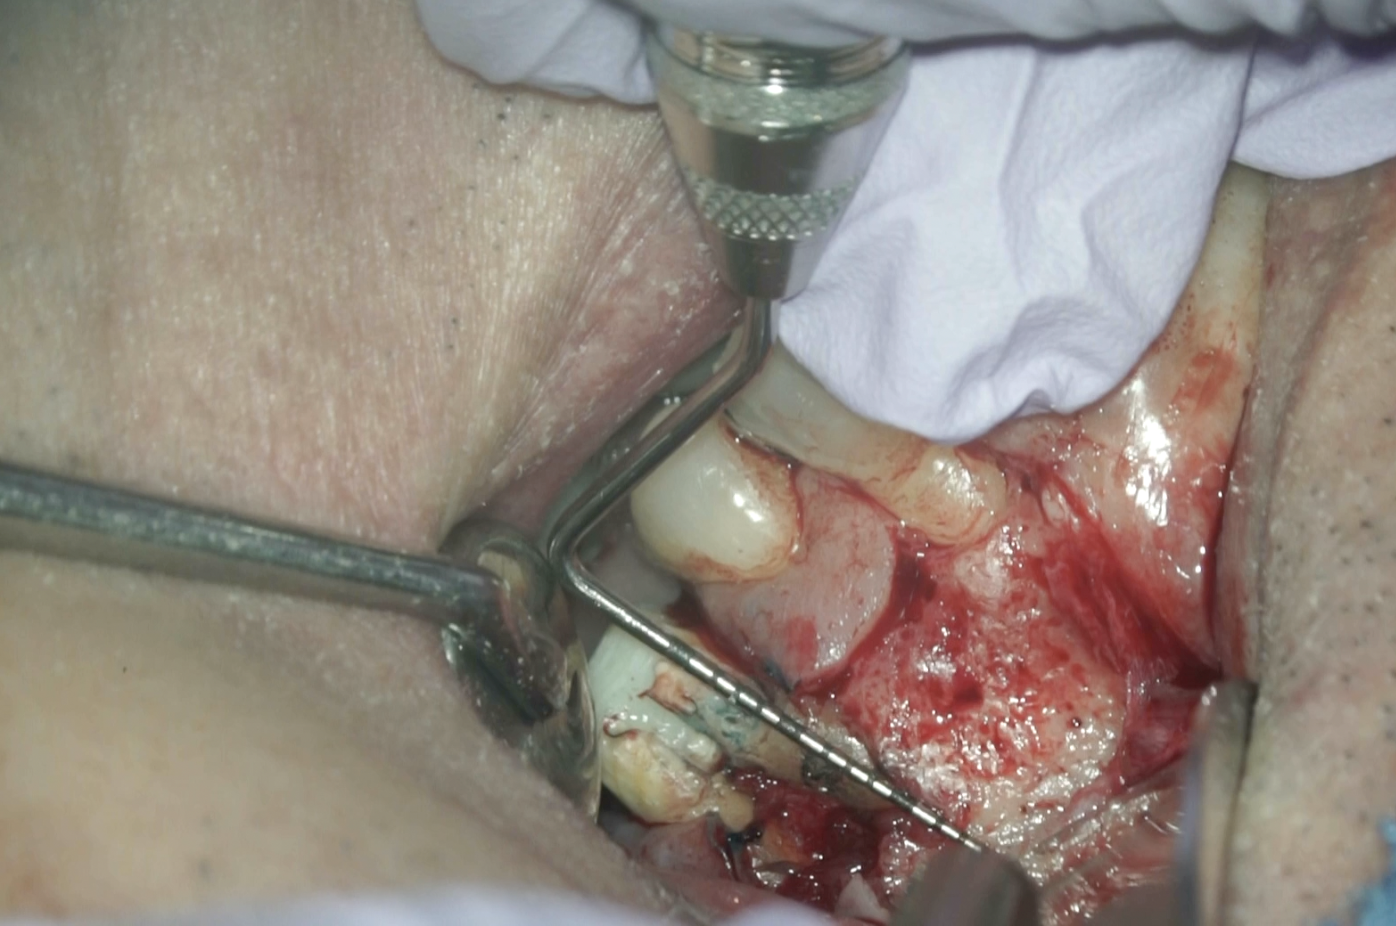

#14 Core build up→MB Apicoectomy(2026.1.30)

MBをメチレンブルーで染めるが、

破折の初見はない。

Light Testも行うが、

破折所見は確認できなかった。

ということで、折れていないと言うことを確認し、Root resectionへ進む。

CBCTから当該Apex相当部位を確認しOsteotomyしてRoot resectionし、メチレンブルーで染色した。